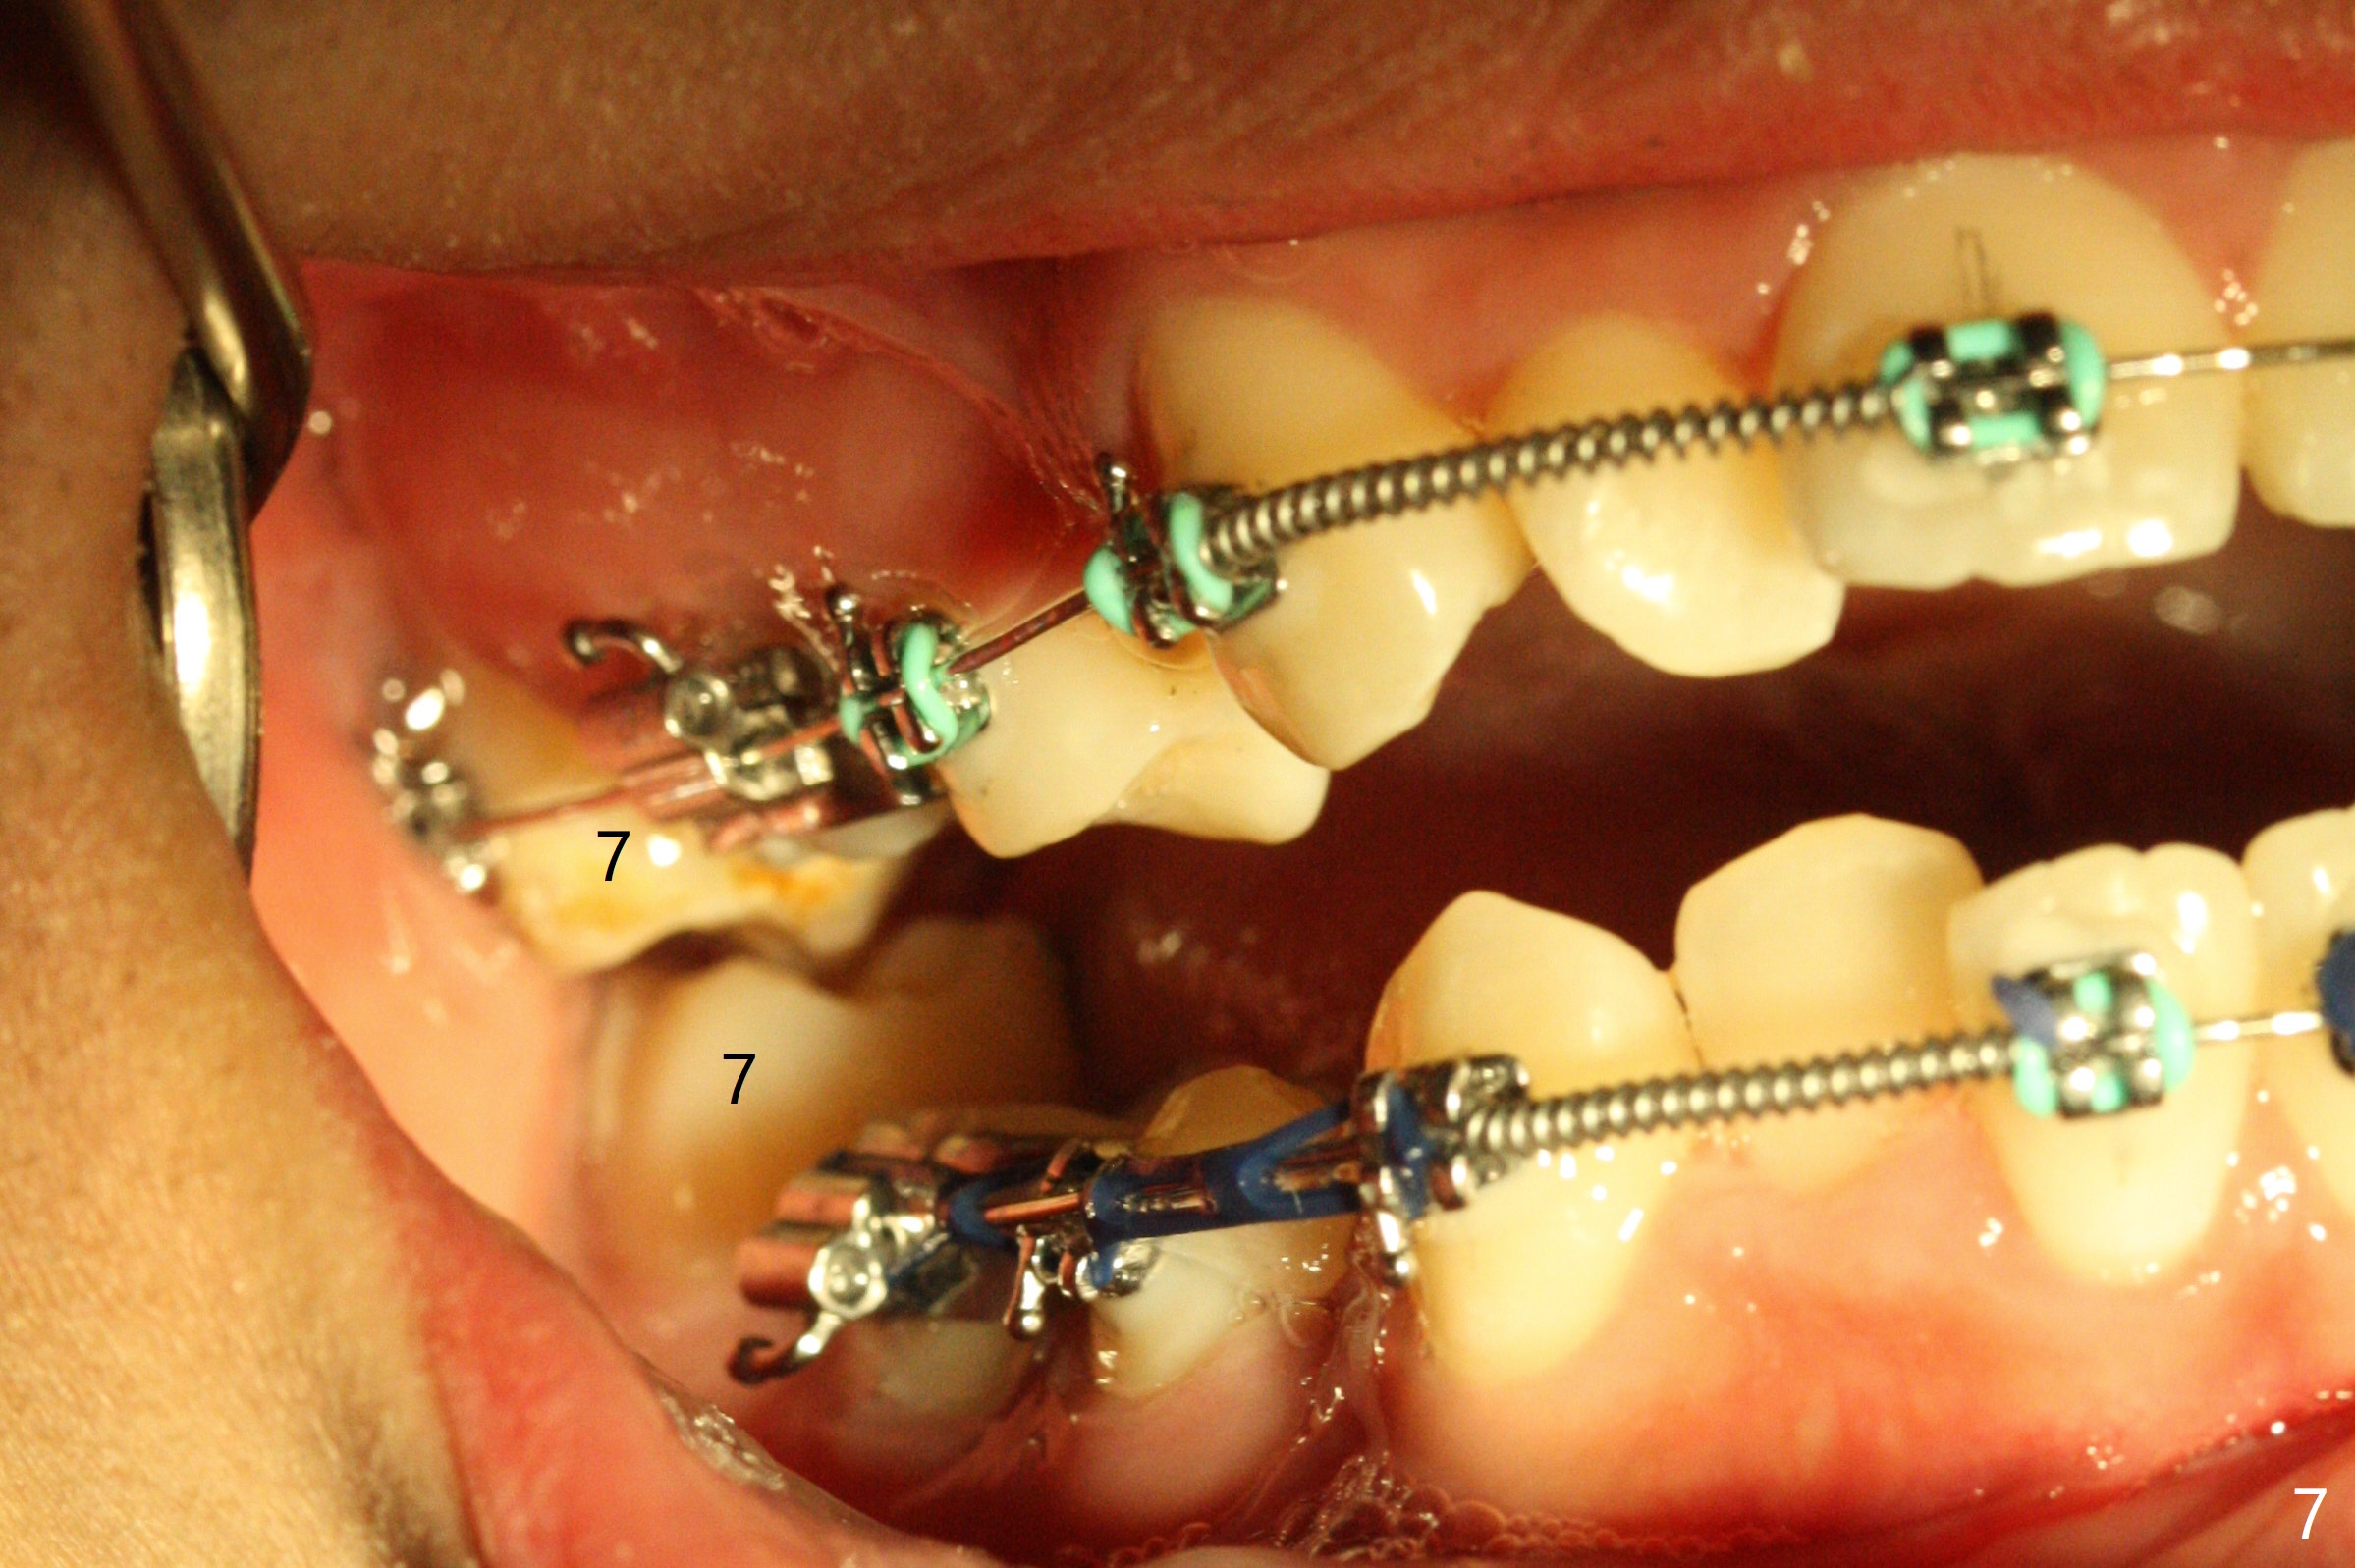

Three months post banding, the cross bite at 7s is corrected; with 7s' supraeruption and 6s' infraocclusion (because of occlusal composite (just removed), Fig.7,8), anterior open bite occur. Next visit place brackets in L7s with flexible wire. While 2 mechanisms are applied to gain more space for LR2 (Fig.9 *, ^), a special mechanism is utilized to correct LL2 cross bite (space gained). If the space for UR2 (Fig.10) is insufficient next appointment, what should we do? Otherwise, what should be done?